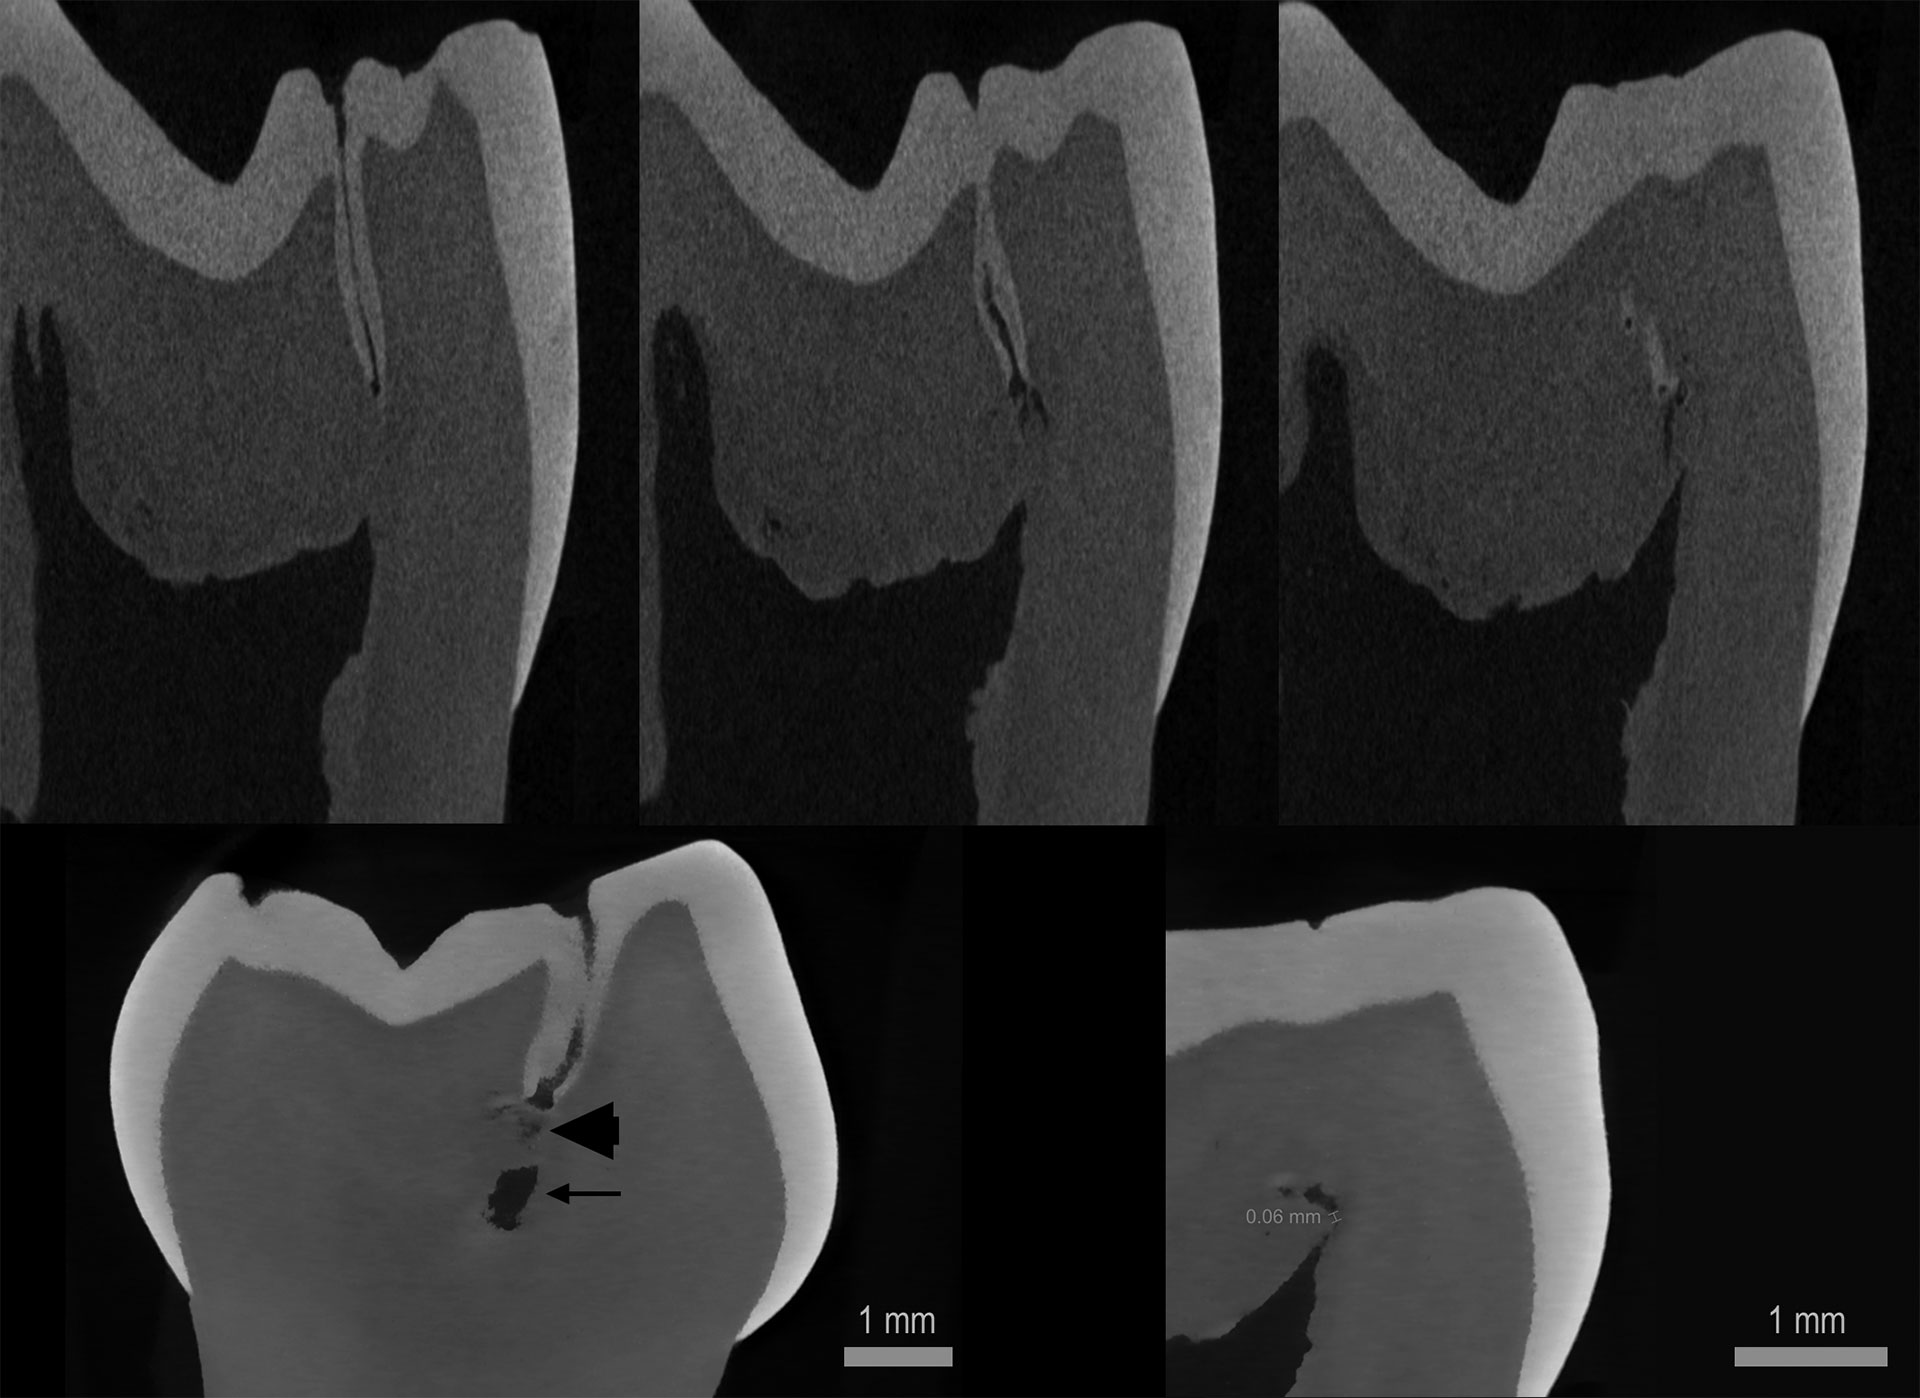

Etter ekstraksjon ble tannen undersøkt med mikro-CT (Bruker Corp. Skyscan 2211 Multiscale) ved Klinisk forskningslaboratorium, Institutt for klinisk odontologi, Universitetet i Oslo. Bildene avslørte en emaljedekket, smal okklusal invaginasjon i kronens distale del, med meget nær relasjon til det distale pulpahornet (figur 3). Nær pulpahornet, som var normalt i motsetning til hva CBCT-undersøkelsen indikerte, manglet invaginasjonen emaljedekke. I henhold til Oehlers klassifikasjon for dens invaginatus (DI) ble mikro-CT-funnene klassifisert som DI type I [1].

Figur 3. Bildeutsnitt fra mikro-CT-undersøkelsen.

Øverst: Tre sagittale snitt viser dens invaginatus, med åpning okklusalt i bildet til venstre og invaginasjonens mer og mer pulpanære utbredelse mot høyre. Merk den meget smale, emaljekledde okklusale inngangen (venstre bilde) og mangel på emalje samt mer uregelmessig form på invaginasjonen i dypet nærmere det distale pulpahornet (bildet i midten og bildet til høyre).

Nederst: Skrå koronalt snitt til venstre. Pilhodet viser den dypeste delen av invaginasjonen og pilen viser pulpahornet. Sagittalt snitt til høyre viser minste målbare avstand fra invaginasjonen til pulpahornet, 0,06 mm.